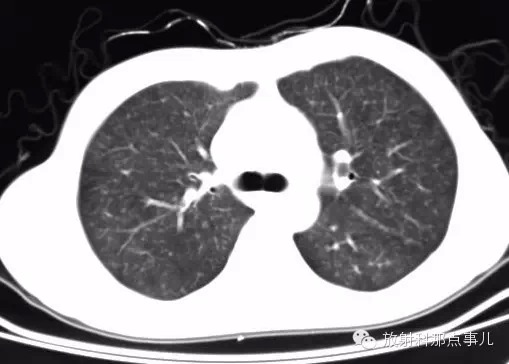

影像表现

1.胸片示双肺网状纹理,弥漫分布粟粒样病灶,由上至下病灶逐渐增多。

2.CT示双肺网状纹理,弥漫分布粟粒样病灶;HRCT示左肺上叶舌段肺气囊。